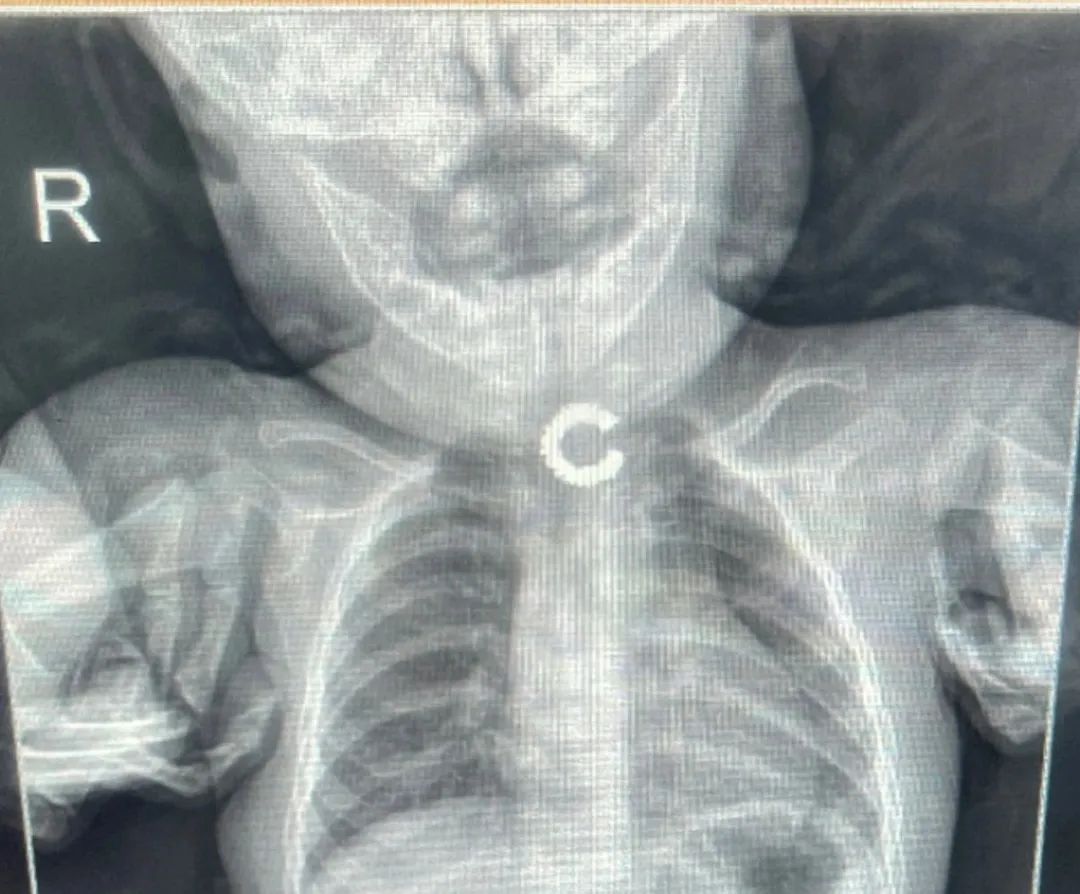

当天,两位焦急万分的家长怀抱哭闹不止的婴儿紧急转院至阿勒泰市人民医院。经询问得知,宝宝在玩耍时不慎将耳环放入口中,导致耳环嵌顿在食管,随即出现呻吟、哭闹和烦躁不安等症状。家长发现后,第一时间带孩子前往当地医院,当地医院排片明确诊断为食管上段环形齿轮状异物,建议转至阿勒泰市人民医院就诊。

接诊后,钟强明副院长迅速组织科内会诊。在充分讨论并再次进行影像学检查后,医疗团队明确了异物的位置、大小、形态以及与周边脏器的关系,同时排除了食管穿孔及出血等并发症,确诊为“食管异物”。考虑到患儿年龄太小,情况危急,若不及时取出异物,极有可能引发食管黏膜水肿、缺血、穿孔、出血等危及生命的严重并发症,医疗团队决定立即实施异物取出术。